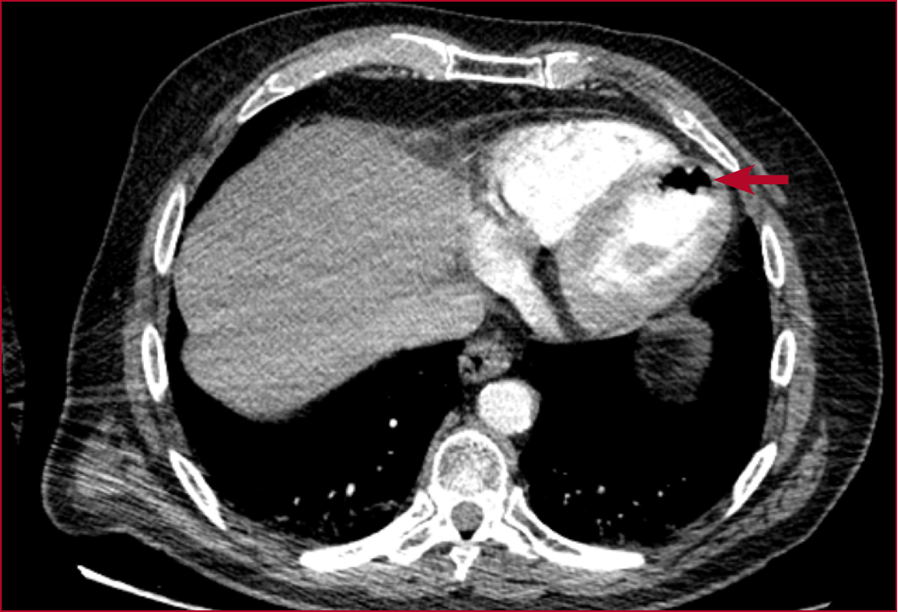

Figura 1. Tomografía computarizada de tórax

con contraste intravenoso, corte axial a nivel del corazón y grandes vasos. Se

observa aire intraluminal dentro de las cavidades cardíacas (flecha),

compatible con embolia aérea cardíaca secundaria a la punción-aspiración

pulmonar.